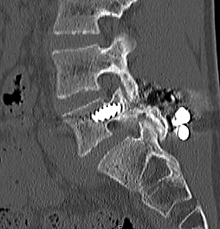

【術前】

CT検査で関節突起部に腰椎分離症を認めています。若年者の腰痛の原因となります。

【術後】

CT検査で関節突起部の骨移植を伴う分離部修復術を施行し骨癒合が得られています。